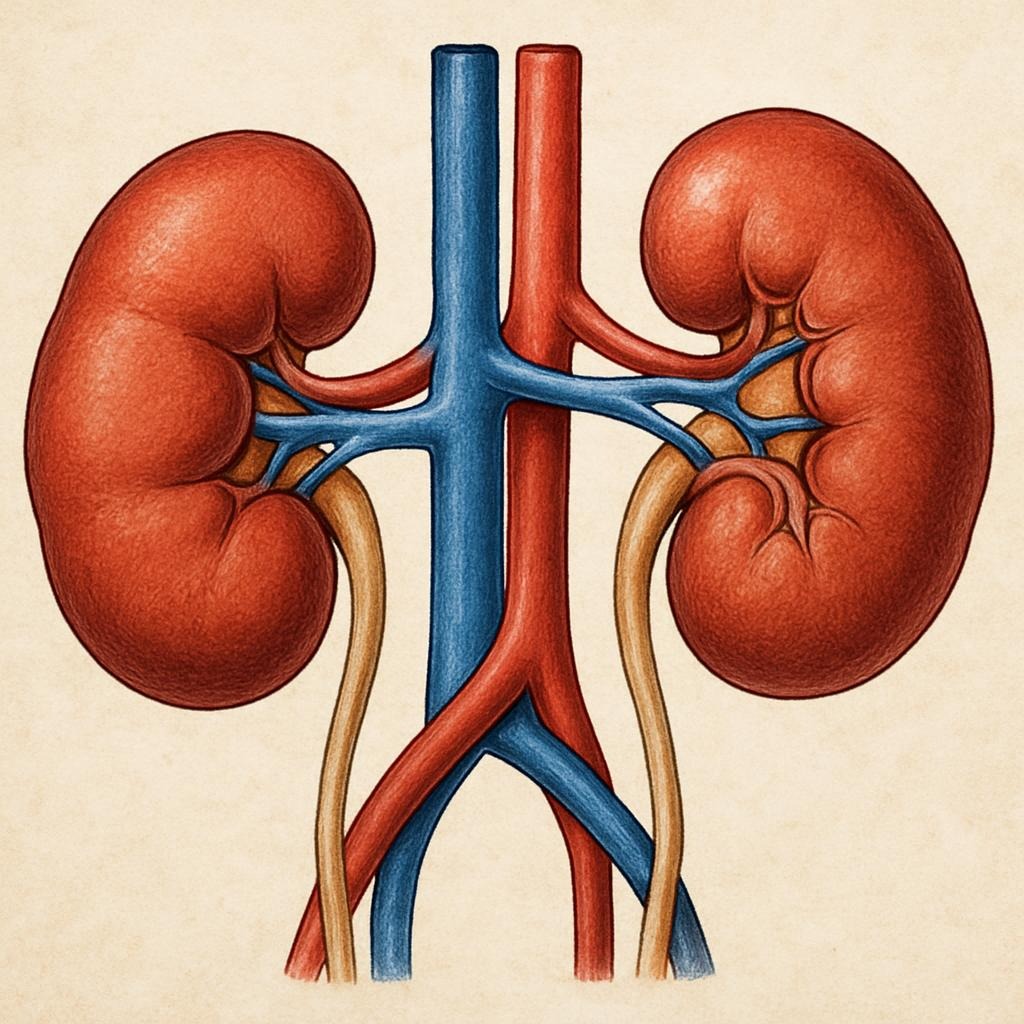

Kidney disease is a common problem affecting about 10% of the world’s population. The kidneys are small but powerful bean-shaped organs that perform many important functions. They are responsible for filtering waste products, releasing hormones that regulate blood pressure, balancing fluids in the body, producing urine, and many other essential tasks. There are various ways in which these vital organs can become damaged. Diabetes and high blood pressure are the most common risk factors for kidney disease. However, obesity, smoking, genetics, gender, and age can also increase the risk. Uncontrolled blood sugar and high blood pressure cause damage to blood vessels in the kidneys, reducing their ability to function optimally.